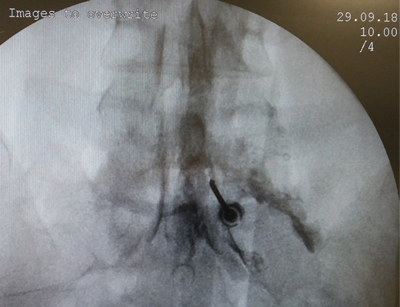

Los procedimientos fueron realizados en sala de operaciones, con anestesia local con lidocaína al 0,5 %, mediante abordaje interlaminar parasagital homolateral al dolor en los espacios L4-L5 o L5-S1, con aguja de Tuohy número 17 o 18, 3½ o 4¾ pulgadas según la complexión física del paciente, con identificación del espacio epidural mediante pérdida de resistencia con suero fisiológico. Se utilizó iopamiron como medio de contraste para visualizar el epidurograma (Figuras 1 y 2).

Fig. 1. Enfoque radiológico anteroposterior de la inyección de contraste en el espacio epidural, durante una inyección epidural de esteroides mediante el abordaje interlaminar parasagital derecho a nivel del espacio L5-S1.